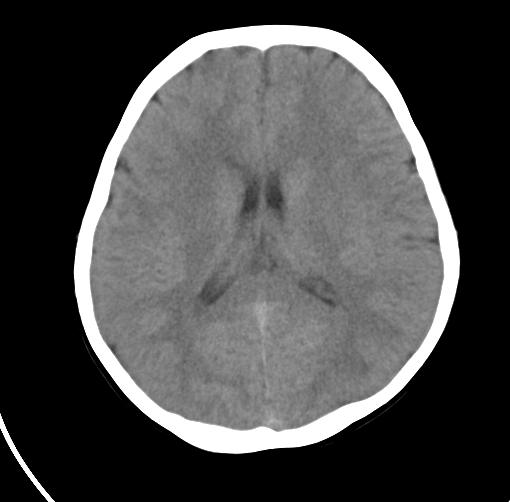

以下是引用sunjh2266在2007-7-31 23:35:00的发言:[br]脉络膜裂,是胚胎发育过程中脉络襞突入侧脑室下角构成脉络丛时形成,位于丘脑下部与海马之间,走行与海马平行。脉络裂内侧通于环池,外侧为侧脑室下角,前面是海马钩及杏仁体,后部与海马沟交通。脉络裂内有参与组成侧脑室脉络丛的脉络膜前动脉及脉络膜后外动脉及其分支走行。[br] mri轴位像,在大脑脚的前外侧多能显示脉络裂的前部,呈左右走行的含脑脊液间隙,前后内外分别与杏仁体、海马、海马钩及侧脑室下角相邻(图1);冠状位像,在扫及脑干的多个层面上,脉络裂均可被清晰显示,因而是显示脉络裂的最佳扫描方式。偏前的部分层面还可见到呈切迹状的海马沟走行于海马旁回内上方;矢状位像,海马旁回上方可见一分叉状裂隙,类似一斜卧的“入”字,接近水平走行的一撇为脉络裂,而由后上向前下走行的一捺为从扣带沟延续而来的海马沟。[br] [br]